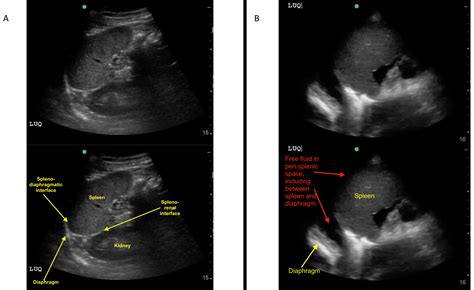

An ultrasound is then conducted to visualize internal organs and structures. The ultrasound technician will apply a gel to the patient's skin and use a transducer to capture images. This step is crucial for examining the heart, abdomen, and other areas of concern.

• fast examination ultrasound

• fast exam ultrasound trauma